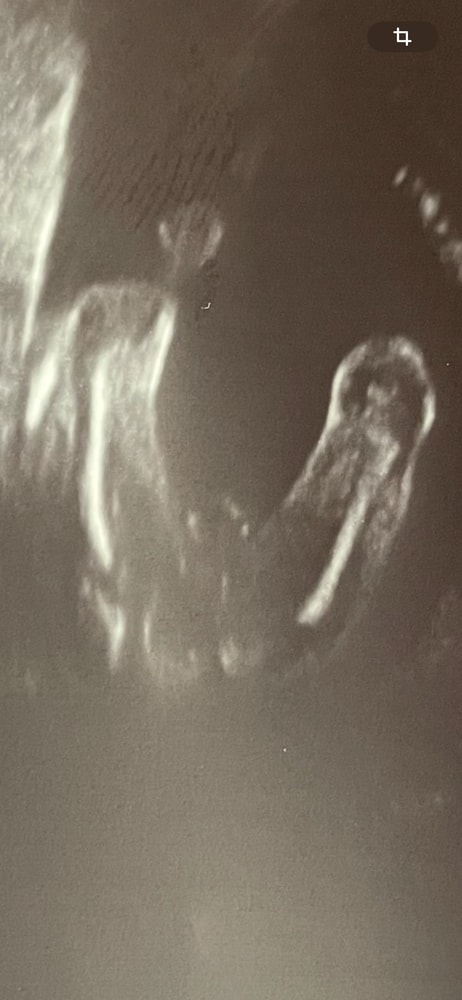

В итоге решила совместить платный контрольный УЗИ с процедурой узнавания пола. Врачу отдала конверт, попросив не говорить, но она сразу же сказала, что тут прям очевиден пол. Я пошутила, что обычно так говорят, когда мальчик, она говорит, ну да, крепкая мошонка. Сфотографировала ее:

Но после начались полтергейсты. Врач за полчаса ни с одного ракурса так и не нашла какие-либо признаки полового члена, так как между ног лежит пуповина. Потом в конце сказала, что вообще ей теперь кажется, что это девочка, так как у девочек на таком сроке могут быть довольно выпирающие губы.

Сейчас смотрю на фото: кажется, что как будто две половые губки, хотя в моменте с экрана (издалека), казалось, что это кругленькая такая мошонка. Да и странно вообще не найти признака полового члена рядом с мошонкой даже с нижнего ракурса.

UPD от 08.10.2025: на скрининге с вероятностью 99% сказали, что это девочка :)